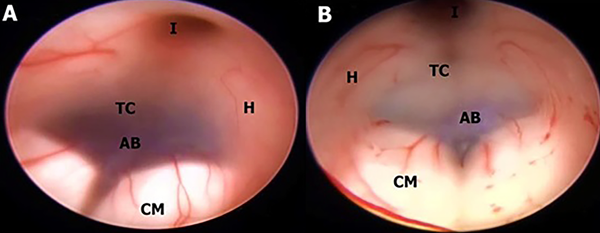

En este estudio fueron halladas 10 variedades anatómicas del piso anterior del tercer ventrículo, las cuales son en orden de frecuencia: piso opaco o grueso 54,90% (Figura 1), piso parcialmente borrado 29,41% (Figura 2), intervalo prepontino pequeño 23,53% (Figura 3), piso estrecho 17,65% (Figura 4 A-B), piso herniado 17,65% (Figura 5), piso delgado 11,76% (Figura 6), basilar elevando el piso 1,96% (Figura 4C-D), adherencias interhipotalámicas 3,92% (Figura 7), fenestración espontánea 1,96% (Figura 8), y piso sin reparos anatómicos 1,96% (Figura 9). Las primeras 7 según la descripción de Sughrue, a la cual se sustituye banda premamilar por adherencias interhipotalámicas, descriptas por Phillips4, fenestración espontánea al hallarse ausencia de PTV u ostomía espontánea como en la Fig. 8, reportada por Parmar5, y se introduce otra categoría no reportada, piso sin reparos anatómicos cuando no se pueden diferenciar los cuerpos mamilares ni el receso infundibular. En la mayoría de los casos se detectaron 2 o más variedades.

Figura 1: Piso opaco en diferentes etiologías de hidrocefalia. A; Mujer de 74 años con estenosis acueductal en cuya imagen endoscópica no se puede visualizar estructuras de la cisterna interpeduncular a través del piso. B; Acercamiento de A constatándose opacidad. C-D Hombre de 16 años con hidrocefalia congénita, portador de DVP, con disfunción de la misma, con agenesia incompleta del Septum Pellucidum y presencia de Cavum septum Pellucidum en C y piso opaco y estrecho más CM de tipo kissing en D. E; Masculino de 49 años con antecedente de meningitis tuberculosa, con hidrocefalia comunicante, con disfunción de DVP. F; Hombre de 49 años con HIC talámico izquierdo más hemoventrículo. Se realiza lavado endoscópico y evacuación de HIC por estereotaxia. Se evidencia piso grueso con petequiado ependimario a nivel del tegmentum y coágulo obliterando acueducto de Silvio. CM kissing. C caudado; CM cuerpo mamilar; Co coágulo; CSP cavum septum pellucidum; FM foramen de Monro; Fx fórnix; H hipotálamo; I Receso infundibular; LT lámina terminalis; Q quiasma; R receso premamilar; SP septum Pellucidum; T tegmentum mesencefálico; TC Tuber cinereum.

En cuanto al tiempo de clínica de hidrocefalia, hubo 32 casos de hidrocefalia aguda (HA) y 19 casos de hidrocefalia crónica (HC). Se determinó, a su vez, en la forma de presentación aguda una mayor frecuencia de piso opaco (n 23/32, 71,8%) y de piso estrecho (n 8/32, 25%). En tanto que en los casos de HC predominó la presencia de piso delgado (n 6/19, 31,58%), el cual se observó exclusivamente en esta categoría, con 0 casos en hidrocefalia aguda. El resto de las variedades de piso se halló en una frecuencia similar en la hidrocefalia aguda y crónica. La asociación del piso opaco con el tiempo de clínica de hidrocefalia fue estadísticamente significativa, con un odds ratio de 7,15 (p 0,001469). Es decir que se observó una frecuencia de piso grueso 7 veces mayor en los pacientes con hidrocefalia aguda en comparación con los que exhibían una hidrocefalia crónica.

En 43 de las 51 cirugías se realizó una Tercerventriculostomía Endoscópica. La dificultad para realizar la fenestración, en base a mayor tiempo quirúrgico y empleo de múltiples instrumentos para alcanzarla, se vio con mayor frecuencia en los pisos de tipo opaco, con intervalo prepontino reducido, estrecho y herniado, pero en el análisis individual de Chi-cuadrado solo se correlacionaron de forma estadísticamente significativa la presencia de un piso grueso, incrementando la dificultad del procedimiento 15 veces (p 0,00041), y la presencia de un piso parcialmente borrado reduciendo el nivel de dificultad con un odds ratio de 0,0615 (p 0,00092).

Con respecto a la disposición de los cuerpos mamilares, la presencia de la forma “kissing” se asoció a una probabilidad 5 veces mayor del hallazgo de un piso grueso (p 0,025).

Las variaciones observadas con mayor frecuencia están en el grosor del piso y en su posición. En los casos de dilatación ventricular aguda, por ejemplo, en la hidrocefalia inducida por tumores de fosa posterior (Figura 7 A-B) o por disfunción valvular (Figura 1 C-D), e hidrocefalia postinflamatoria (figura 3C) el PTV puede estar sin distensión y extremadamente grueso, sin ningún tipo de transparencia y con los cuerpos mamilares difícilmente reconocibles. Por el contrario, en los casos de ventriculomegalia de larga data debido a hidrocefalia crónica, como los que se puede observar en algunos pacientes con estenosis acueductal, el PTV puede estar extremadamente distendido y protruir hacia la cisterna interpeduncular debido al gradiente de presión entre el tercer ventrículo y el espacio subaracnoideo, y ser delgado y transparente.3,6,7 Esto es consistente con la teoría que dice “el grado de hidrocefalia es inversamente proporcional al grosor del PTV”. Un piso delgado significa que la perforación puede lograrse sin mucha fuerza o manipulación, reduciendo el riesgo de lesión del complejo basilar y del hipotálamo.3 A pesar de esto, un piso grueso se puede presentar también en hidrocefalia crónica. Rohde2 reportó una incidencia de 16% de piso grueso y Iaccarino8 de 48%. Un piso engrosado se ha asociado con aumentos en el tiempo quirúrgico, contusiones e incidencia de diabetes insípida debido a una manipulación quirúrgica y estiramiento más enérgicos del hipotálamo. El riesgo de daño a la arteria basilar y las arterias pequeñas del tuber cinereum también aumentaría, aunque no existen cifras oficiales que apoyen esto.3